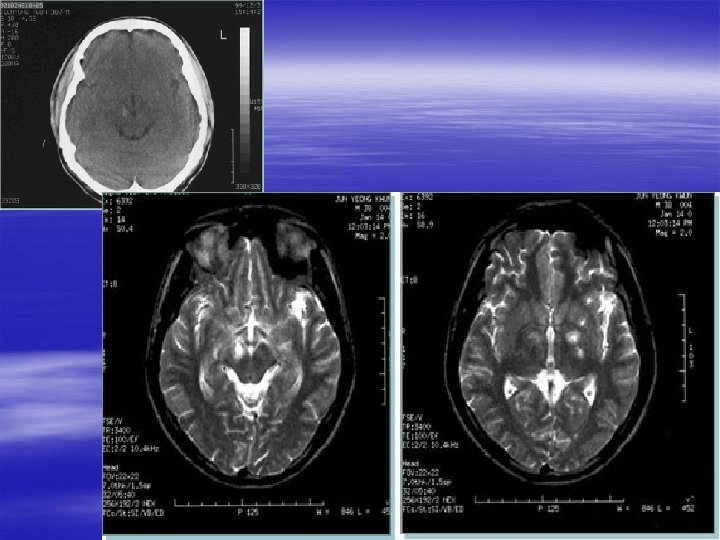

Specific Head Injuries § Diffuse Axonal Injury – Disruption of axons in white matter and brainstem – Injury occurs immediately and is irreversible – Seen after MVC or shaken baby syndrome – Usually have persistent vegetative state – CT usually normal – MRI with multiple, diffuse abnormalities